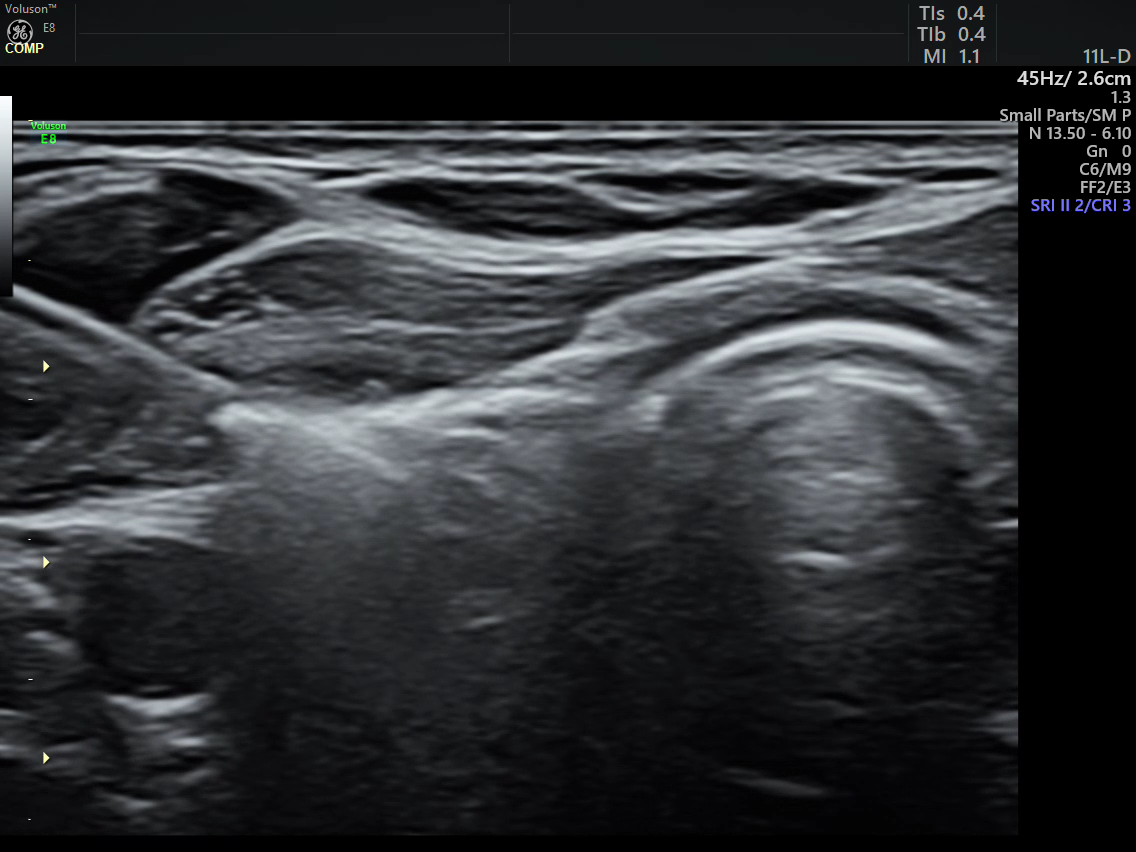

术中,在高频超声的实时引导下,通过穿刺针水隔离病灶部位与周围组织器官,通过精准导航在完整消融病灶的同时,最大程度避免了对周围正常组织的损伤,仅用时数分钟就完成了整个治疗。术中术后患者未出现声音嘶哑及出血等并发症,术后即刻超声造影显示病灶区无增强,提示消融完全,在住院19小时后患者顺利出院。出院前复查甲状旁腺素12.4pg/ml,呈“断崖”式下降,血钙2.46mmol/L,标志着腺瘤病灶被完全灭活,甲状旁腺功能异常得到纠正,血钙恢复到正常水平,治疗效果显著。

消融过程 消融后造影病灶无增强